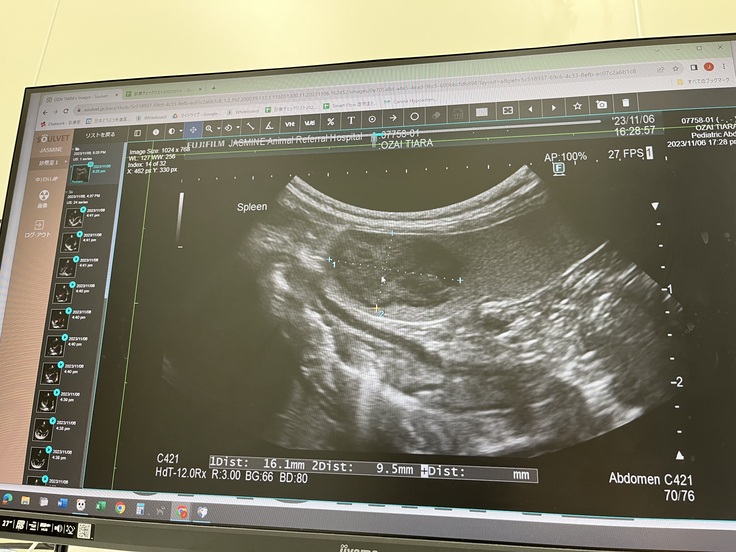

さらに脾臓にリンパ腫も見つかった為

2023.11.15に脾臓の細胞診の検査をし

リンパ腫の疑いとの判断になり

そちらは僧帽弁閉鎖不全症の手術後に

経過を診て、摘出手術になりました。

※こちらが脾臓の腫瘍のレントゲンです。